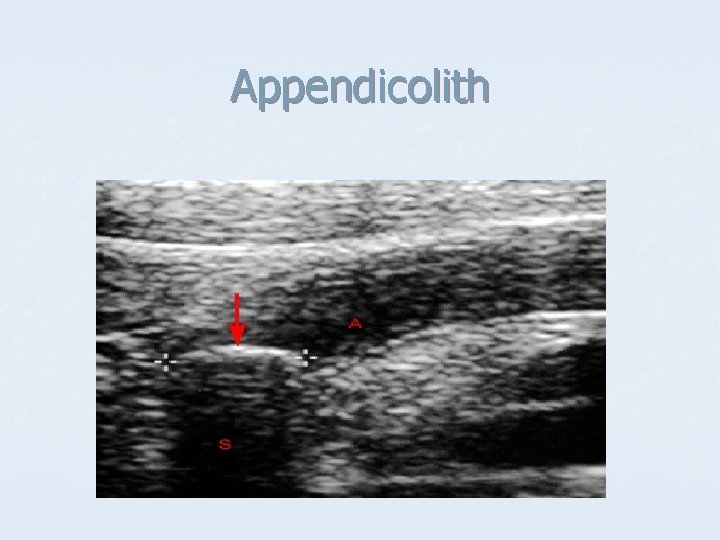

Appendicolith